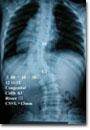

先天性椎体畸形

先天性椎体畸形系胚胎时椎体发育过程中分节不全或形成不全所引起。

2.椎体形成不全 它可以部分或全部形成不全。部分单侧椎体形成不全时,椎体出现楔形或斜方形。X线片上表现切工作为一个小的发育不全椎体验生活 。半椎体由单侧完全形成不全所引起。半椎体与相邻椎体可以不分布、半分节或分节。分节半椎体导致椎体生长不对称,尤其一侧出现二个半椎体时可出现严重脊柱侧凸,当椎体后方出现半椎体时则导致后凸成角畸形。半分节半椎体与相邻一个椎体融合,侧凸畸形相对较轻。不分节半椎体与相邻两个椎体融合,一般不引起进展性脊柱侧凸。根据Nasca报告一起60例半椎体病人,将其分为6型:①单纯多余半椎体:可与相邻一个或两个椎体融合。发生在胸椎时可有椎弓根及多余肋骨。②单纯楔形半椎形。③多个半椎体。④多个半椎体伴有一侧椎体融合。⑤平稀半椎体:两侧均有数量相等的半椎体,一般不引起脊柱侧凸。⑥后侧半椎体:易引起后凸畸形。

详细记录病人的身高,包括站高及坐高,胸背的旋转及侧凸程度,双下肢社经检查结果,是否合并其它畸形如先天性心脏病、Sprengel畸形、腭裂等。X线片可明确椎体畸形类型,应包括全脊柱正侧位片,以便初步估计术中可能矫正的角度。若有神经症状者,必须行脊髓造影,有条件者做MRI检查,除外脊髓纵裂或栓系综合征。